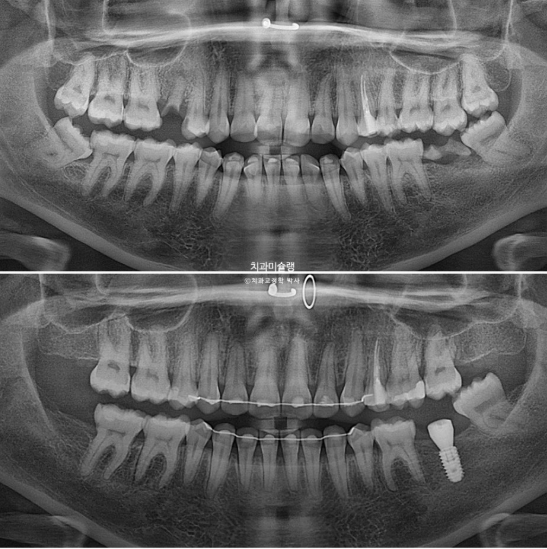

In the maxilla, one premolar had decayed to the point where only the root remained.

In the mandible, a molar was in a similar condition, with only the root remaining.

For the missing mandibular molar, ideally, the wisdom tooth could be moved forward to replace it. However, the wisdom tooth already showed root inflammation and was not in a healthy condition. Therefore, we decided to extract the wisdom tooth and proceed with orthodontic treatment, followed by implant placement in the molar region.

For the mandibular arch, we decided to extract the second premolar affected by dental caries.

At this stage, the implant fixture was first placed in the mandibular posterior region, followed by intrusion of the supra-erupted opposing tooth.

Throughout the orthodontic treatment period, there was no evidence of root resorption, and root parallelism remains excellent.